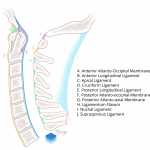

- Offset of the lateral masses of C1 with respect to the occipital condyles consistent with atlanto-occipital subluxation

- Bilateral atlanto-occipital subluxation (extensive ligamentous injury subsequently confirmed on MRI)